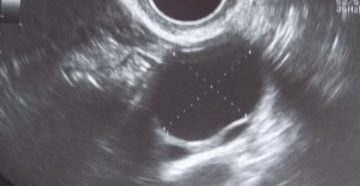

В яичнике жидкость: что это и причины возникновения Жидкость в яичнике — одна из патологий…